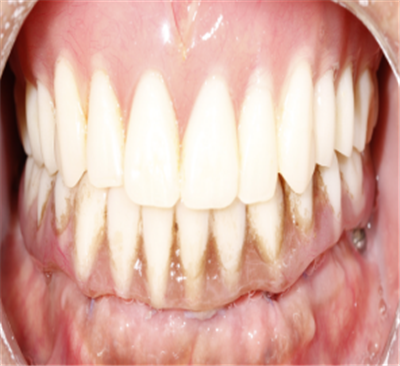

今年刚过60岁的赵先生,上颌牙早就全掉光了,下颌也只剩几颗松松垮垮的牙,稍微硬点的东西都不敢碰。原本最爱吃的锅包肉、酱骨头,现在只能看别人吃。?

更让赵先生惊喜的是,手术一结束,团队成员立刻为赵先生取模,制作即刻义齿。赵先生试戴后表示十分满意,实现了当天拔牙、当天种牙、当天戴牙,当天使用。

从无法正常进食到轻松享用美食,从遮遮掩掩到自信开口,赵先生生活不再被牙齿问题困扰,重新找回了吃饭的幸福感,现在这种能自由享受美食、自在与人交流的状态,让他每天都觉得踏实又开心。?